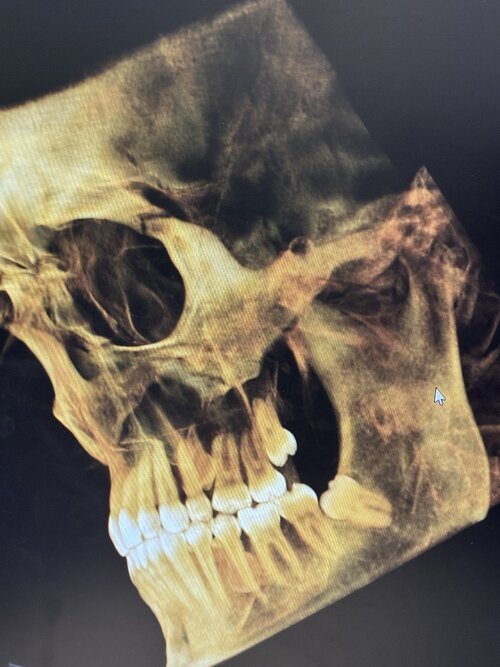

i want to get bimax to ascend my lips and make my nose go from slightly downturned to straight asf.

I’m consulting with Pagnoni. I know he usually says surgery first is okay but that seems to be a little problematic since he seems to be very liberal about who can do it.

And if I do have a bite issue… could I technically pull my jaws forward at equal advancement without getting braces?

If your bite is good and you have occlusion it’s possible to advance without braces